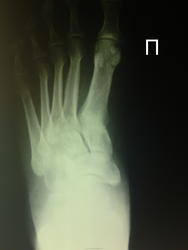

Больная 50 лет, жалуется на боль в правой стопы. Направлена к травматологу. Факт травмы отрицает. Пальпаторно диффузная отечность и болезненность правой стопы.

По направлению травматолога сделали снимок правого голеностопного сустава в 2-х проекциях:

и правой стопы в прямой и косой проекциях:

Смутило некоторое вздутие по заднему краю большеберцовой кости и участок разрежения костной ткани кубовидной кости в области сочленения с V плюсневой костью.

Кубовидная - в порядке.

"Разрежение" (кажущееся) - наблюдается и слева - результат укладки и свойств Rg-луча "перебивать" (высвечивать) тонкие ткани (в наблюдении - задний край

большеберцовой, не закрытый задним контуром медиальной лодыжки). Кортикальная пластинка не изменена!